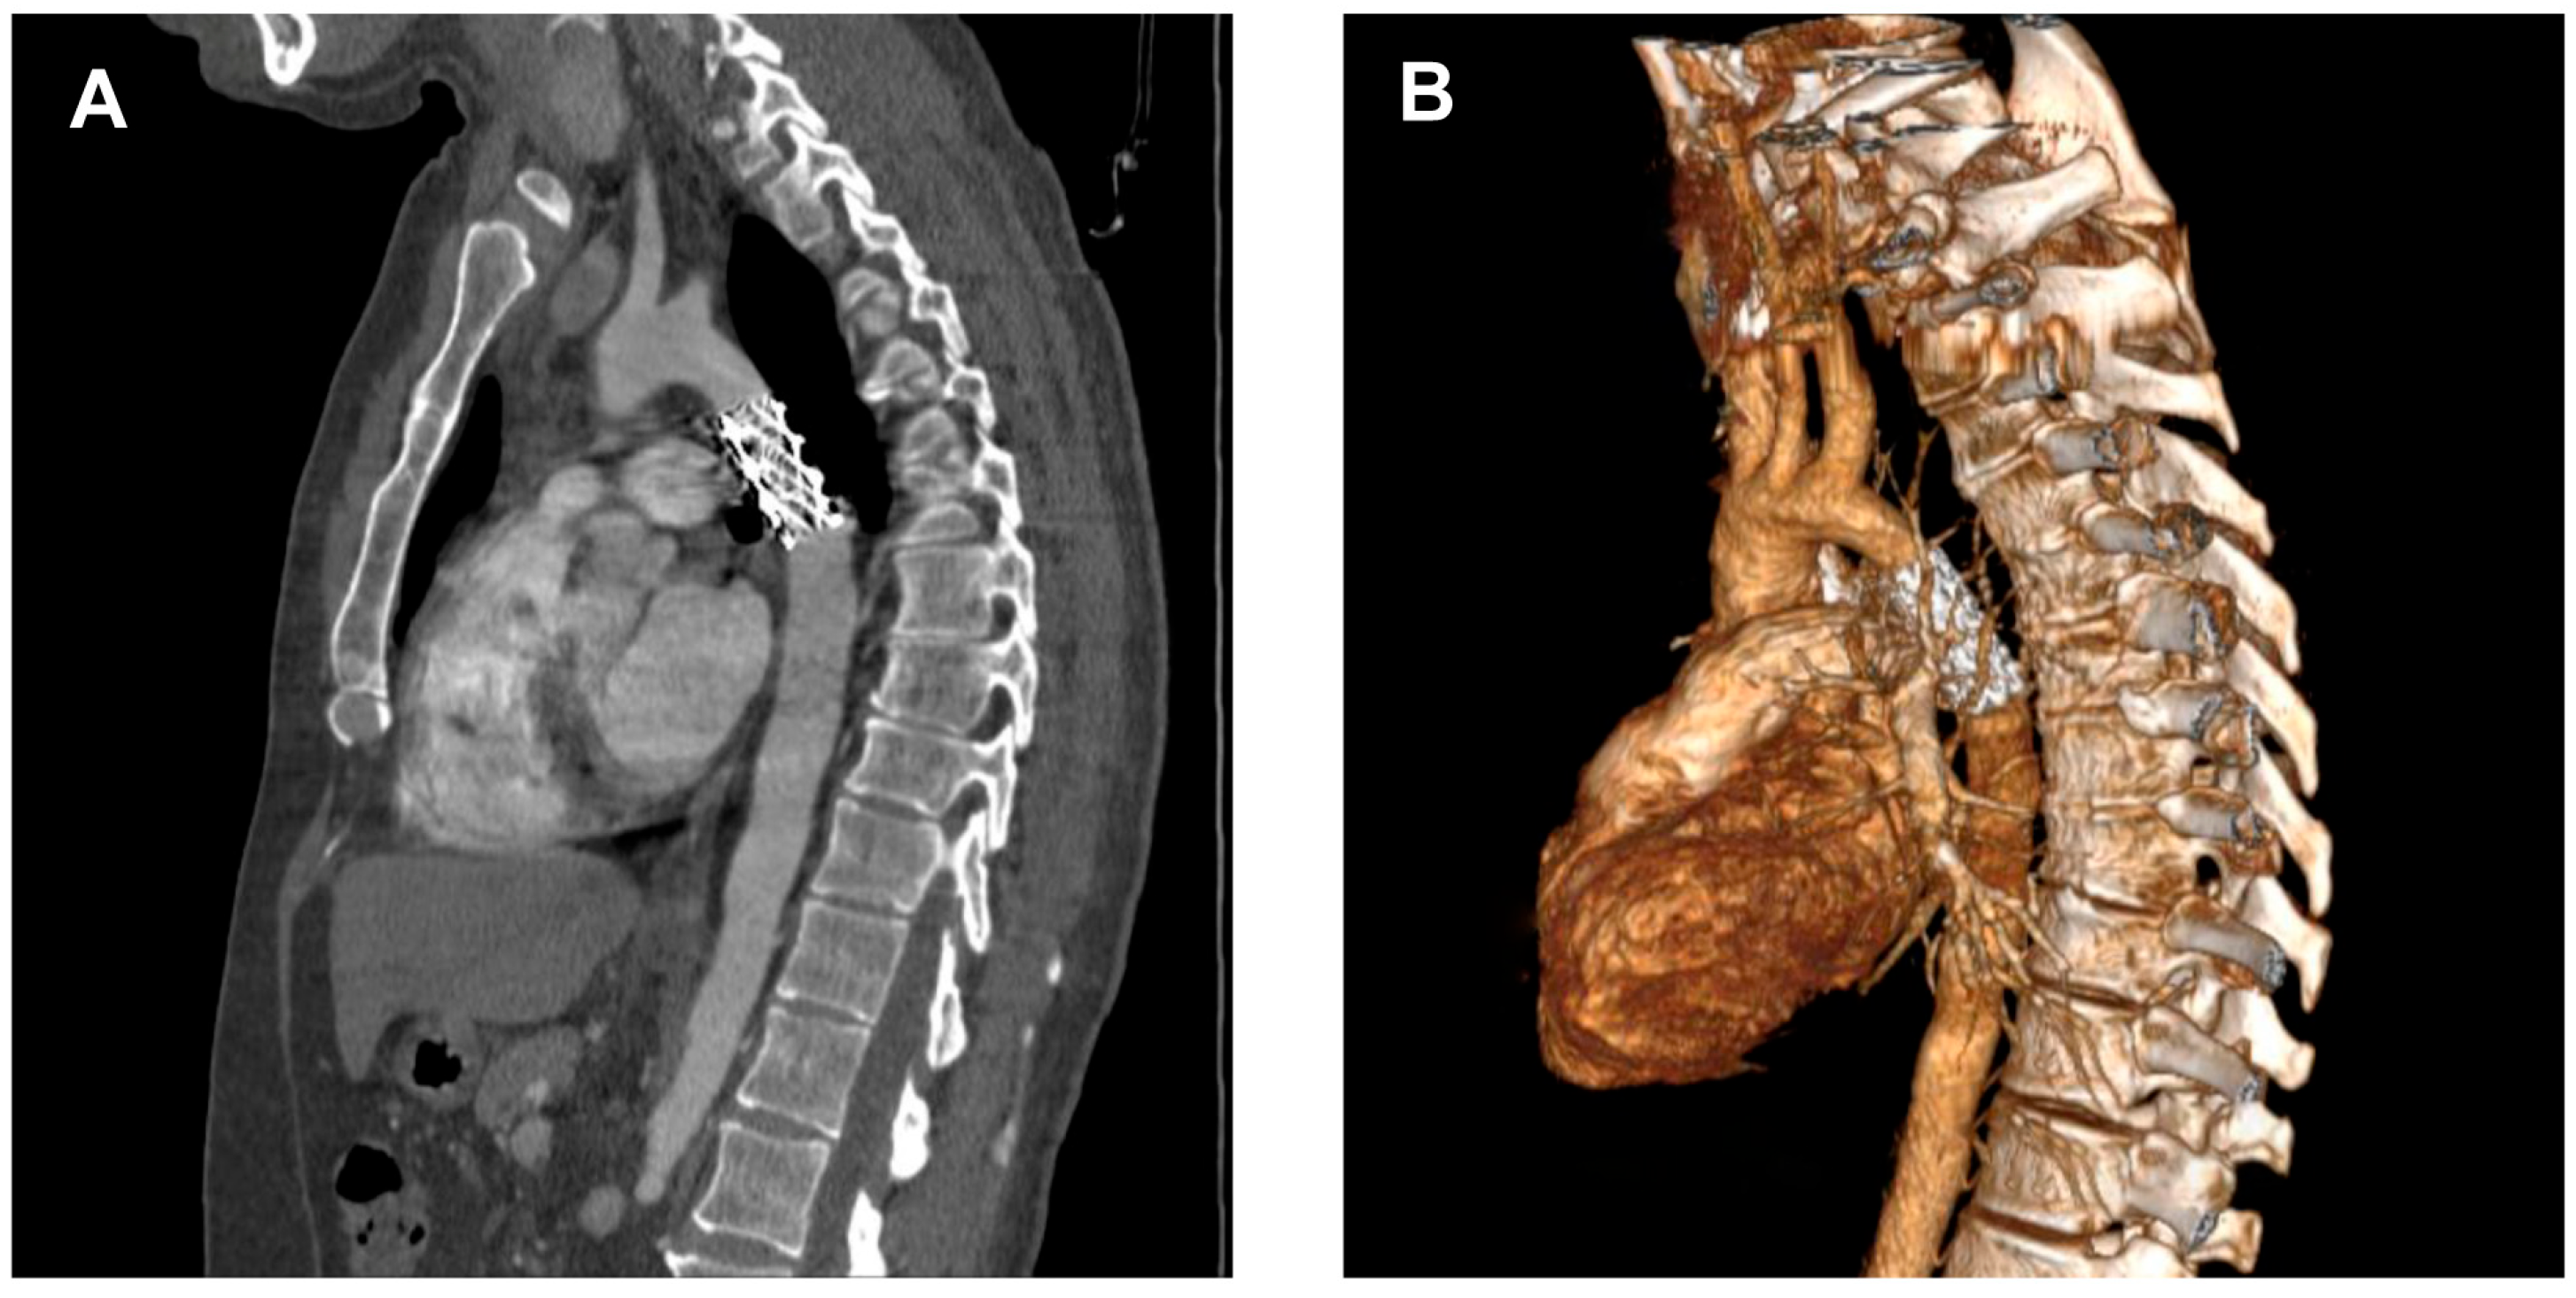

2.1. Diagnosis

2.2.6. Imaging and Hemodynamic Assessment

| CT angiography | Computed tomography angiography |